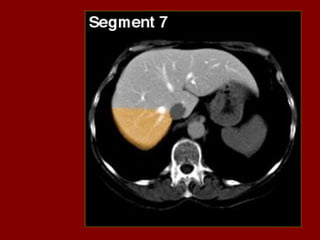

Ac Colo ascendente AP Nível de ar fluido do estômago Ao Aorta Az Veia ázigo CA Tronco celíaco cc Cartilagem costa! CD Dueto cístico CHA Artéria hepática comum CHD Dueto comum CL Lobo caudado fígado D Diafragma DBM Músculos profundos do De Colo descendente D2 Parte descendente do duodeno D3 Parte horizontal do duodeno E Esôfago FL Ligamento falciforme GB Vesícula biliar HA Artéria hepática Hz Veia IMV Divisão da veia mesentérica inf. D IVC Veia cava inferior LC Ramo esq. do diafragma LG Glândula supra-renal esq. LHV Veia hepática esquerda LIL Lobo inf. Esq. do pulmão LRV Veia renal esquerda LK Rim esquerdo LU Ureter esquerdo LL Lobo esquerdo do fígado MHV Veia hepática média P Pâncreas PA Antro pilórico do estômago